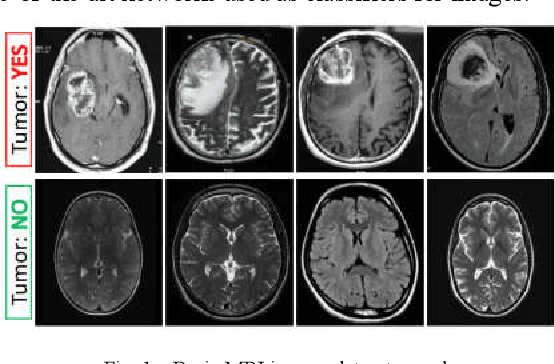

Abstract:Diagnosing Brain Tumor with the aid of Magnetic Resonance Imaging (MRI) has gained enormous prominence over the years, primarily in the field of medical science. Detection and/or partitioning of brain tumors solely with the aid of MR imaging is achieved at the cost of immense time and effort and demands a lot of expertise from engaged personnel. This substantiates the necessity of fabricating an autonomous model brain tumor diagnosis. Our work involves implementing a deep convolutional neural network (DCNN) for diagnosing brain tumors from MR images. The dataset used in this paper consists of 253 brain MR images where 155 images are reported to have tumors. Our model can single out the MR images with tumors with an overall accuracy of 96%. The model outperformed the existing conventional methods for the diagnosis of brain tumor in the test dataset (Precision = 0.93, Sensitivity = 1.00, and F1-score = 0.97). Moreover, the proposed model's average precision-recall score is 0.93, Cohen's Kappa 0.91, and AUC 0.95. Therefore, the proposed model can help clinical experts verify whether the patient has a brain tumor and, consequently, accelerate the treatment procedure.